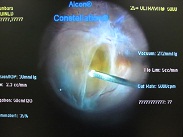

今日は水晶体亜脱臼による緑内障発作の患者様がいらっしゃり、お昼休みに緊急手術をさせて頂きました。

入院のほうがいいかな?と思いましたが、あいにく満床なので、日帰りで。

先ほど電話をしたら、手術前のような痛みは全くなくなったとのこと。

よかった。一安心です[:楽しい:]